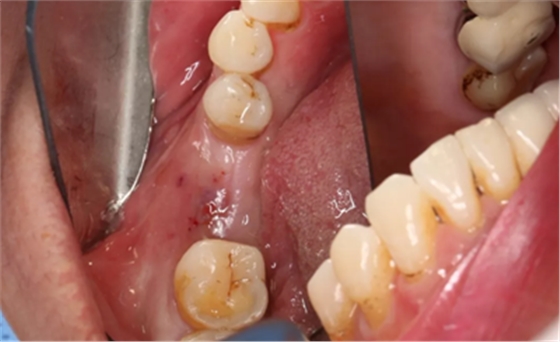

9、术后六月复诊,种植前

软硬组织愈合良好并上皮化,牙槽嵴形态保存较好。缺牙间隙:12mm,合龈距:7mm。

(摄于2017年2月15日)